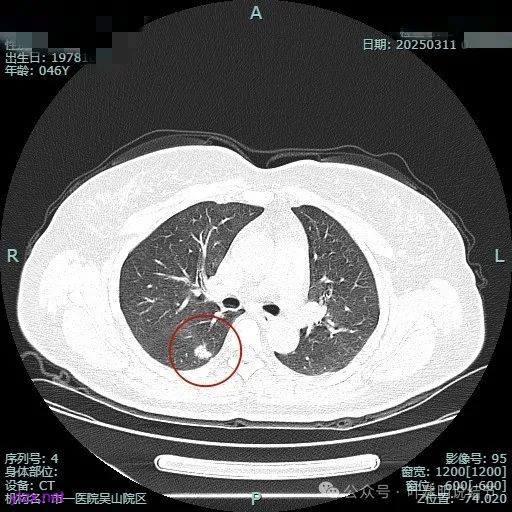

时间很快到了2025年3月,结友又来我门诊复查,我还以为她在别处开了刀了呢,结果并没有,说是与家人商量后决定吃中药三个月看看能不能好。我们来看看再复查的情况,中药有没有起作用:

总体感觉三处病灶边缘的淡磨玻璃成分好转不太明显了,实性成分较前略显致密点,大小与形态是说不上显著变化的。所以有几点可以肯定:1、消炎没有效;2、中药没有用;3、考虑多原发肺癌,且为浸润性腺癌可能性大些,得手术!